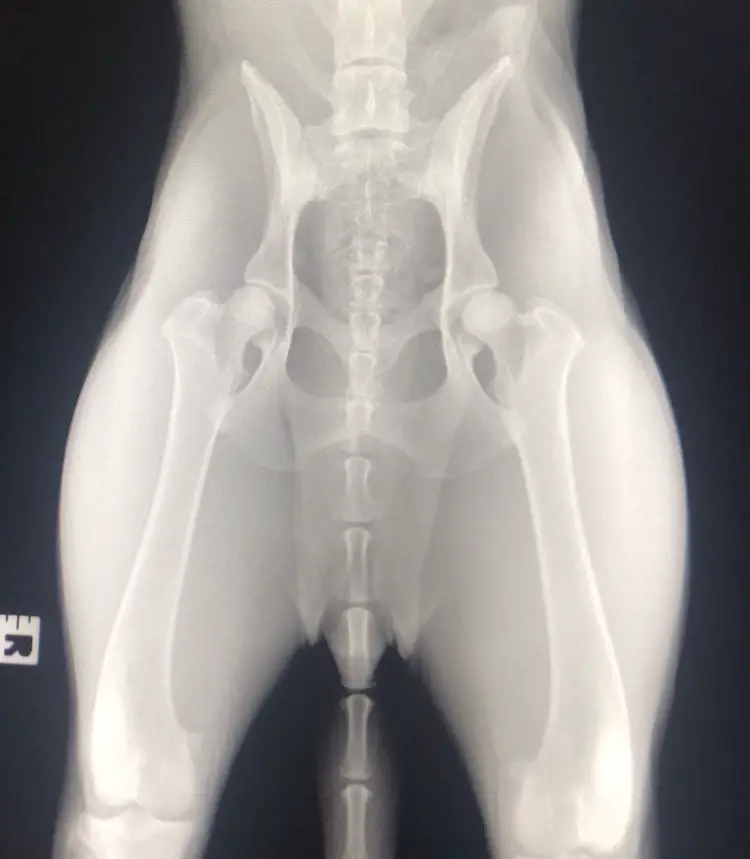

Just had this dog Radiograph by my vet. What are your thoughts? Two year old GSD Bitch

The second x-ray is worse than the first--at least the femurs are correctly rotated and parallel in the first one, while in the second version the pelvis is straight but there's no rotation of the femurs and they are akimbo instead of parallel.

For an example of a beautifully positioned film, check out the one in this thread.

THAT'S what your film should look like, if you asked and paid for OFA-quality hip x-rays.